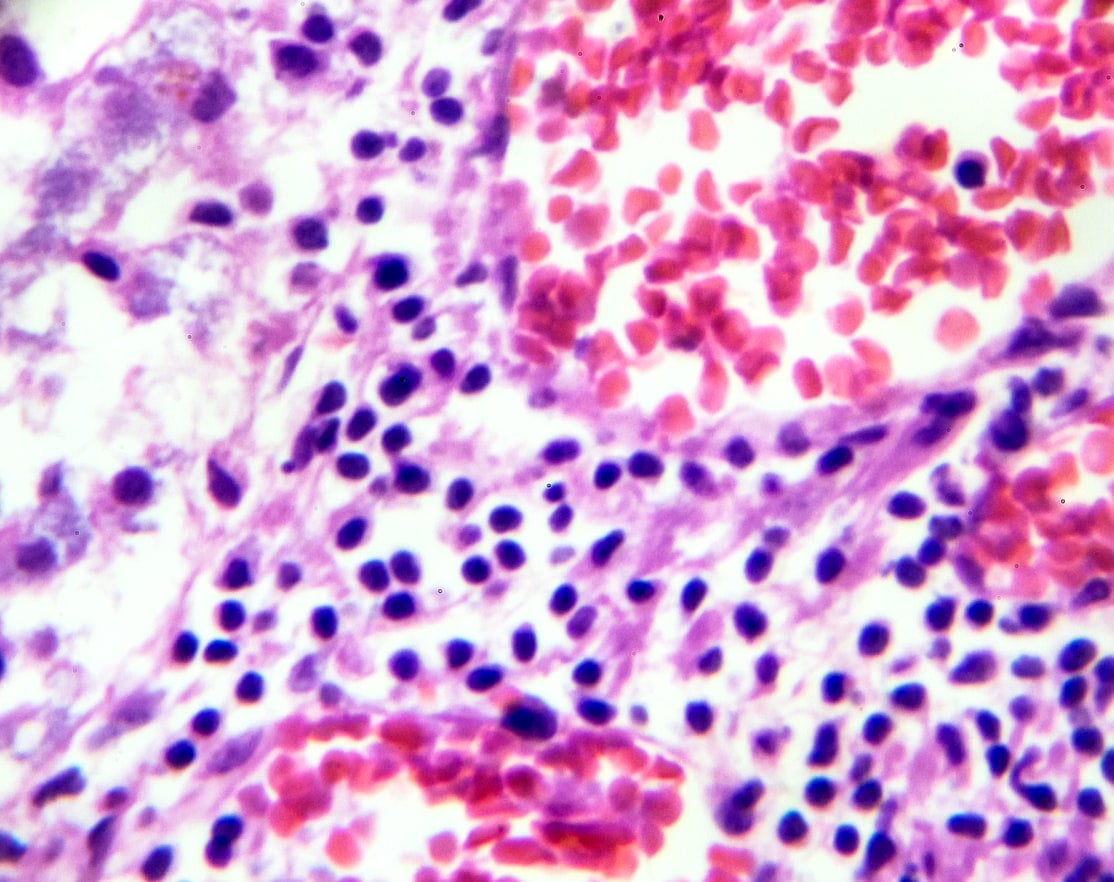

Waldenström Macroglobulinemia

Lipid rafts play a crucial role in Waldenström's macroglobulinemia (WM), a type of indolent b-cell non-Hodgkin lymphoma characterized by the accumulation of lymphoplasmacytic cells and the overproduction of monoclonal immunoglobulin M (IgM). In WM, lipid rafts contribute to aberrant signaling pathways, survival, and disease progression by clustering receptors and signaling proteins that are central to the malignant phenotype.